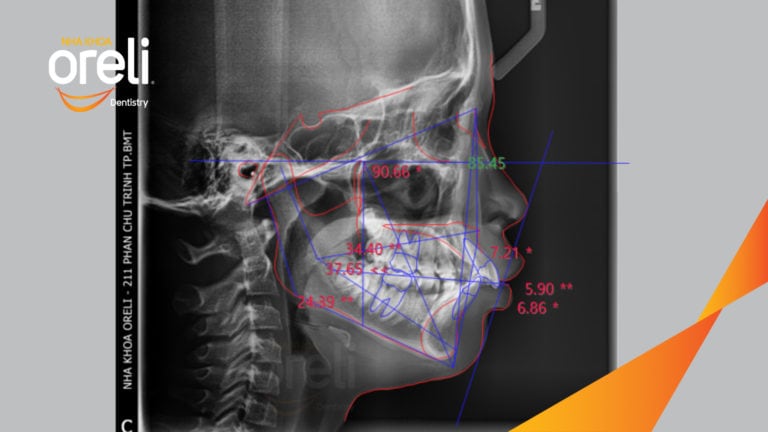

Ca niềng chỉnh cắn sâu hô lùi cằm cho kết quả nụ cười và góc nghiêng đẹp ở Oreli Niềng răngCắn sâuHôLùi cằm Xem thêm

Ca niềng chỉnh cắn sâu nặng kèm cắn chéo vùng răng sau kết quả thực tế tại nha khoa Oreli Niềng răngCắn sâu Xem thêm

Ca niềng chỉnh cắn sâu không nhổ răng kết quả cười đẹp sau hơn hai năm tại Oreli Niềng răngCắn sâu Xem thêm